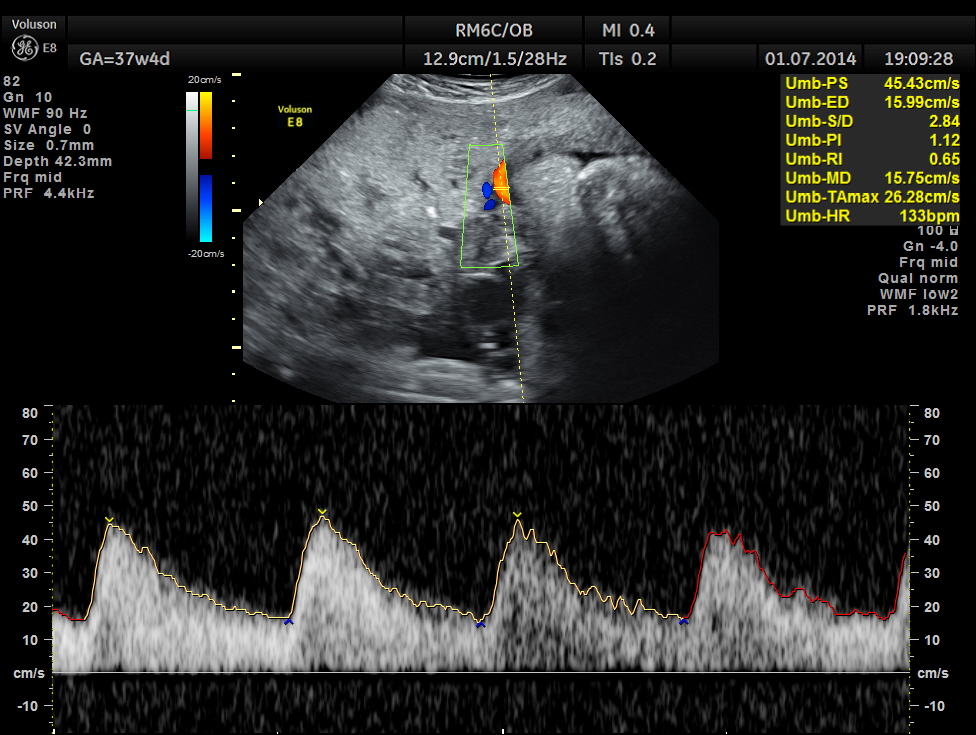

Spectral Doppler pictures are given below.

Umbilical arterial arterial P.I. and R.I. are high for the GA. and the cerebro placental ratio appears to be borderline > 1.0 and < 1.1 for the R.I.

The spectral Doppler pictures are given below

Umbilical artery R.I . AND P.I. appear to be normal now. The cerebro placental ratio is also normal.